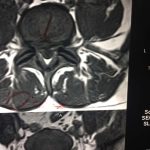

- α

- β

- γ

- δ

- ε

- στ

- ζ

- η

- θ

- ι

Εικόνα 4 α,β,γ,δ, Αξονική τομογραφία της Ο.Μ.Σ.Σ. (Σεπτέμβριος 2017) μετωπιαίες λήψεις (coronal) ε,στ,ζ,η, οβελιαίες λήψεις (saggital) θ,ι, εγκάρσιες λήψεις (axial). Παρατηρείται η σημαντική οστική αραίωση εντός του σώματος του 1ου οσφυϊκού σπονδύλου.